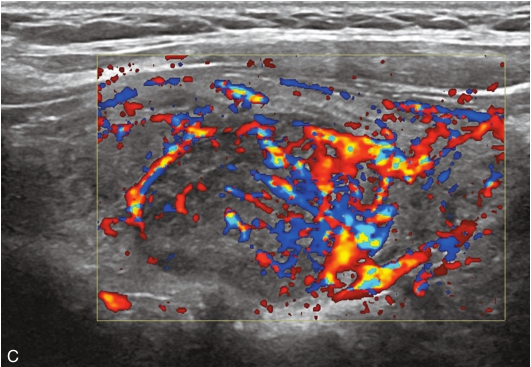

甲状腺右叶中部见一低回声结节,大小约2.0cm×0.9cm×1.7cm,部分边界不清楚,形态不规则,内可见多发点状强回声。CDFI结节内及周边可见较丰富血流信号,见图1-9-7。

图1-9-7 甲状腺髓样癌常规超声声像图

A.甲状腺右叶结节横切面;B.甲状腺右叶结节纵切面;C.甲状腺右叶结节CDFI血流图

甲状腺右叶中部结节超声造影后早于周围组织开始,自周边向中心逐渐增强,达峰时呈不均匀等增强,增强范围较常规超声增大,周边可见不规则环状高增强,结节前方甲状腺被膜连续性中断,之后消退呈明显低增强,见图1-9-8。

甲状腺右叶中部低回声结节伴有多发钙化,边界不清,形态不规则,血流丰富;超声造影后呈不均匀低增强,周边可见不规则环状高增强结节增强范围较常规超声增大,结节前方甲状腺被膜连续性中断,上述特征均提示恶性。

甲状腺髓样癌超声表现多样,微小结节时与乳头状癌表现类似(特别是伴有钙化时),结节较大时与腺瘤表现类似,内部液化与丰富的血流信号是其鉴别点,边缘分叶状也是其常见的表现类型,超声造影时结节可呈高增强、等增强及稍低增强,周边不规则环状增强及范围扩大可进行良恶性鉴别,本例结节前方甲状腺被膜连续性中断,提示甲状腺前被膜受侵,得到术后病理证实。实验室检查中降钙素、CEA升高对于确诊具有重要意义。